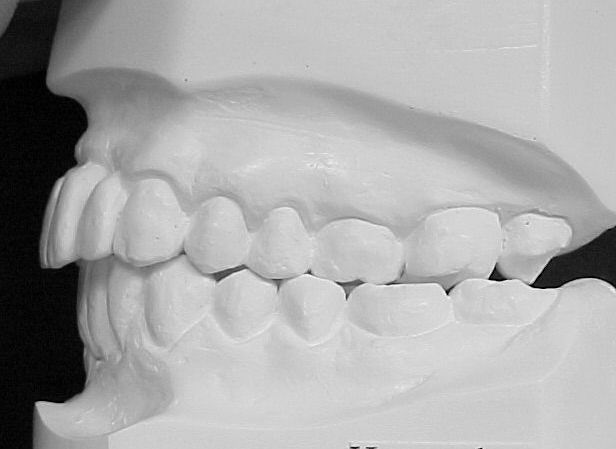

Modelos de estudo antes do tratamento

|

Modelos em gesso após o tratamento